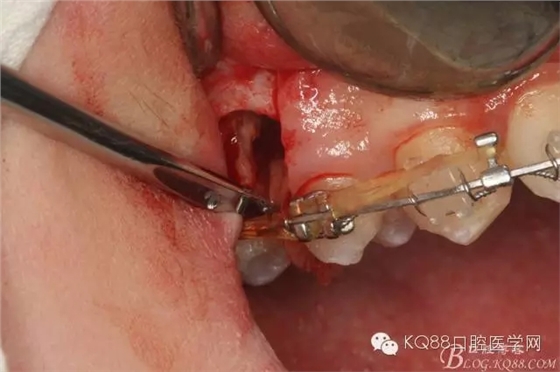

圖1.術(shù)前患者的口內(nèi)照片:16與14之間有約2mm間隙,矯治器已經(jīng)安裝到位。

圖8.因16與14合面的間隙僅2mm左右,牙根無(wú)法合向脫位,如何考慮15牙根的脫位將是最大問(wèn)題。高速手機(jī)去除牙間隙內(nèi)的覆蓋在15牙根表面的牙齦組織